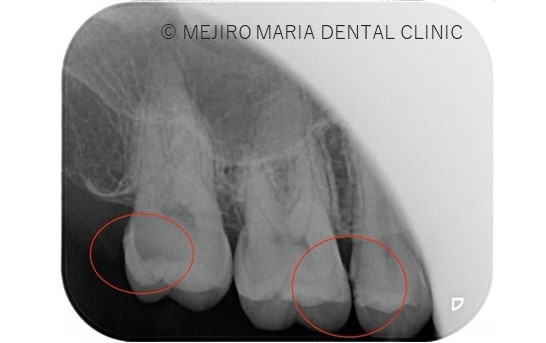

※左画像、赤矢印注釈部分は虫歯箇所を指す。右画像赤丸で囲われたところがう蝕である。

定期検診と歯石除去希望でご来院。他院に3ヶ月〜6ヶ月の間隔で通っていた。しかしながら、初診時の検査にて歯の隣接(歯と歯の間)からのう蝕(虫歯)が多く確認された。患者様本人に症状の自覚はなく、無症状のままう蝕が進行していた。患者様より当院での治療をご希望頂き、処置を開始した。